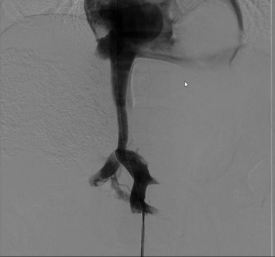

经过充分的术前准备,手术在我院杂交手术室进行。首先,黄纪伟教授、廖明恒副教授团队在下腹作一小切口,将肠系膜上静脉分支暴露;然后,吴浩教授、魏波副教授消化介入团队将特定的手术器械送入肠系膜上静脉,在肠系膜上静脉近门脉端与下腔静脉之间放置覆膜支架建立分流通道,类似于开闸泄洪,使部分淤滞的肠道、脾脏血流直接进入体循环,降低门静脉系统压力,控制和防止静脉曲张破裂出血,促进腹水吸收。

手术历时1+小时,过程顺利,术后肠系膜上静脉造影见支架分流通畅,门体静脉压力梯度由术前20mmHg降至术后8mmHg,手术达到预期目标。术后患者情况稳定,复查CT显示支架通畅,侧支循环消失,5天后好转出院。患者后续需要长期服药治疗包虫病灶。

(左图:术前CT重建 右图:术后CT重建)